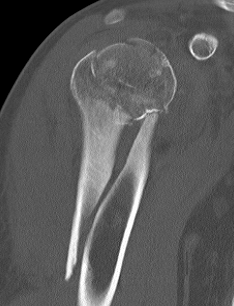

proximal humerus fracture Background ORIF with locking plate Arthroplasty Greater tuberosity fractures Lesser tuberosity fractures / avulsions Book traversal links for Proximal humerus fractures ‹ Pectoralis Major Tears Up Background ›